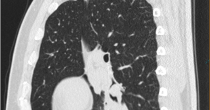

CT矢状位肺窗:右肺下叶阻塞性炎症

影像表现:右肺下叶支气管根部软组织密度结节影,直径约17mm,管腔明显狭窄,FDG摄取增高,SUVmax=3.29;右肺下叶基底段支气管狭窄,并见不规则形实变,内见支气管扩张、充气,FDG轻度摄取,SUVmax=2.18。

印象:右肺下叶支气管根部肿物,FDG代谢增高,考虑肺癌,继发性右肺下叶阻塞性肺不张及阻塞性肺炎。后行支气管镜检查。病理结果为:支气管根部肺癌(黏液表皮样癌)。

尽管肺部癌症的筛查大家认为CT扫描更有优势,但是对于比较复杂的情况,单纯依靠CT图像,肿瘤灶与周围渗出、实变灶很难分辨。而派特CT正好能弥补这个不足,利用肿瘤灶高代谢的特点,结合多平面重组技术,找到其准确位置,不仅可以显著提升支气管镜检病理诊断的准确率,也为后期手术指明了方向。